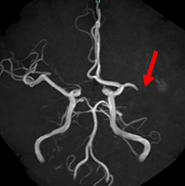

くも膜下出血のCT

【くも膜下出血のCT】

Apoplexy 14

【脳動脈瘤;矢印の部位】

治療の方法は、開頭して動脈瘤にクリップをかけるクリッピングという方法と、コイル塞栓術といって頭を開けないでカテーテルで治療する方法があります。どちらの手段にも有利な点と不利な点があり、当院では動脈瘤の場所、形状、患者さんの状態などに応じて両者を使い分けています。